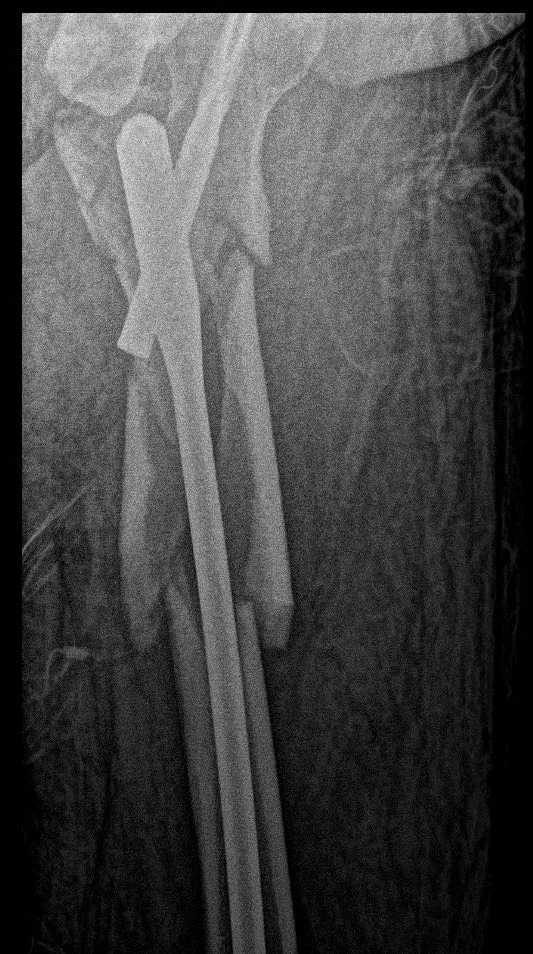

再看看在门诊看到的外院一例相似患者,

为了复位骨折而复位骨折的切开做,当然切开没有绝对的错,早期没有髓内钉的时候,我们也切开做,但这样的切开,就没有创伤骨科理念。

术后2月,远端锁钉都退了。